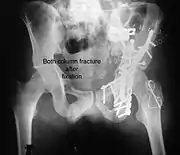

Posterior column and wall fixed using screws and plates

Both column fracture after fixation with screws and plates